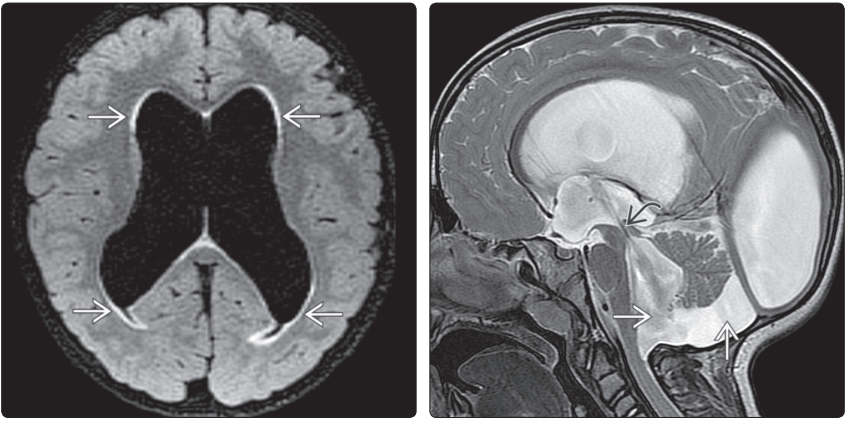

(左图)横断位LFAIRMRI示:第三脑室前隐窝→,正常呈裂隙状。另外,枕叶内侧高信号分别是指环形连接的左枕角↪、囊肿样结构的右枕角 ⇒。(右图)冠状位LFAIR MRI示:枕叶小灶高信号→显示的是环形连接的左枕角,不能误诊为发育不良或损伤

(左图)MR横断位T1WI示:中脑导水管狭窄引起侧脑室颞角→和第三脑室前隐窝↪显著扩张。(右图)MR冠状位T2WI示:包括颞角(左侧显示较好 ⇒,杏仁核下方扩张)在内侧脑室明显扩张。第三脑室↪前隐窝下缘膨胀、壁变薄

(左图)横断位FLAIRMRI示:侧脑室扩张伴间质水肿→。(右图)MR矢状位T2WI示:由第四脑室流出孔和基底池瘢痕(早产儿大面积脑室出血)导致的严重脑积水。双侧脑室显著扩张,导致胼胝体上抬、变长。第三脑室隐窝扩张,导水管狭窄引起的流空现象↪,第四脑室经Magendie孔突出于小脑蚓部下方→